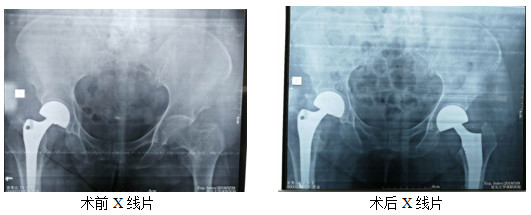

近日,患者姜某某,女性,76歲,因摔傷致左側髖部疼痛4小時入院,行拍片,診斷:左側粗隆間粉碎骨折。因患者年齡偏大,體重較重,右側于入院前兩年在外院行關節(jié)置換手術。家屬慕名來骨科一病區(qū)就診。入院后,立即給予對癥處理,完善各項術前評估,并于傷后第3天行手術治療。過去術后一個半月左右才允許患者下床活動?,F(xiàn)在患者麻醉清醒后就開始患肢活動,術后3天,逐漸在下肢助行器的輔助下進行完全負重活動。對比上次外院手術、康復情況及就醫(yī)體驗,患者及家屬表示非常滿意。

骨科一病區(qū)在創(chuàng)傷、關節(jié)、骨病、脊柱、足踝肩肘外科等骨科領域的治療方面具有豐富的臨床經驗??砷_展各種復雜四肢骨折及關節(jié)內骨折、脫位的手法及手術治療;全髖關節(jié)及全膝關節(jié)置換術;骨不連、急慢性骨髓炎、關節(jié)炎的手術治療。脊柱骨折脫位并截癱的手術治療。頸、胸、腰椎間盤突出癥、椎管狹窄癥的手術治療。四肢骨腫瘤的手術治療。近年來,科室開展了復雜髖關節(jié)病變全髖關節(jié)置換術、椎管內占位性病變的手術治療 、骨關節(jié)炎的保髖、保膝治療等,均具市內先進水平。